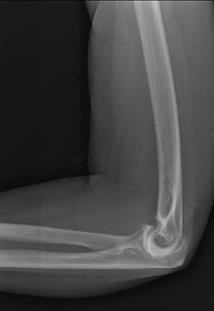

An 85-year-old female with severe rheumatoid arthritis and osteoporosis sustains a highly comminuted, intra-articular distal humerus fracture (AO/OTA 13-C3) after a mechanical fall. She lives independently and uses a walker. Which surgical intervention provides the most predictable pain relief and allows for immediate postoperative weight-bearing through the upper extremity for mobility?

Explanation

In an elderly, osteoporotic patient (especially with a history of inflammatory arthritis like RA) who sustains a highly comminuted intra-articular distal humerus fracture, Total Elbow Arthroplasty (TEA) provides superior outcomes compared to ORIF. It offers more predictable pain relief, earlier return of function, and allows the patient to bear weight immediately (within standard TEA limits, though essential for immediate walker use) without the high risk of hardware failure or nonunion associated with osteoporotic bone.